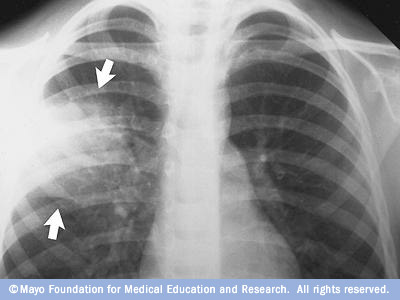

نضع بين ايديكم مجموعة الصور الاضافية على السلايدات التي تم شرحها في X-ray session :

Kerley B line